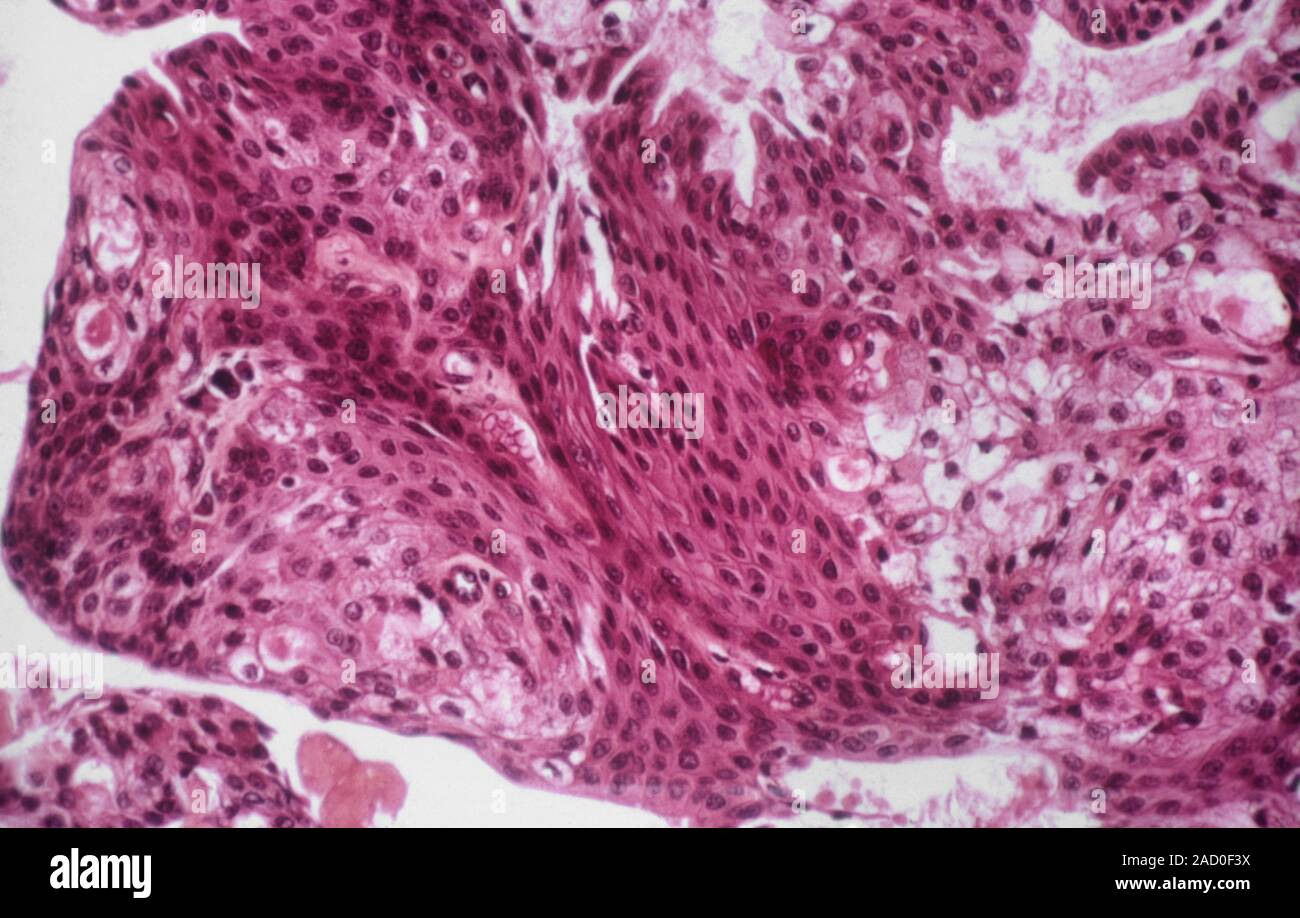

Source: theasnhtp.pages.dev Le cancer des glandes salivaires. Microphotographie lumière d'une section par l'intermédiaire d , Les cancers des glandes salivaires sont beaucoup moins fréquents que les tumeurs bénignes.Le cancer des glandes salivaires le plus courant est le carcinome muco-épidermoïde (un cancer qui affecte les cellules qui forment les glandes salivaires), qui peut se former dans une petite glande salivaire (mineure) sur le plafond de la bouche ou comme une grosseur dans l'une des grandes glandes..

Source: ballotnmehw.pages.dev Le cancer des glandes salivaires. Microphotographie lumière d'une section à travers une glande , Si vous avez un cancer des glandes salivaires, vous vous posez peut-être des questions sur votre pronostic La plupart de tumeurs de la glande salivaire sont bénignes et naissent dans les glandes parotides